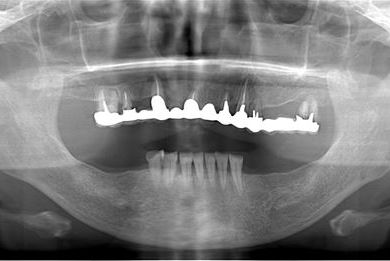

インプラントの症例写真 IMPLANT

インプラント治療+セラミック治療

| 主訴 | 上の奥歯がむし歯で治したい。下の歯が少ないので、インプラントか入れ歯、できれば併用で。 | ||||||||||||||||||||||||||||||||

| 治療方針 | インプラント治療にて、機能的・審美的回復を行う。 | ||||||||||||||||||||||||||||||||

| 治療内容 | インプラント3本、ハイブリッドセラミッククラウン5本 | ||||||||||||||||||||||||||||||||